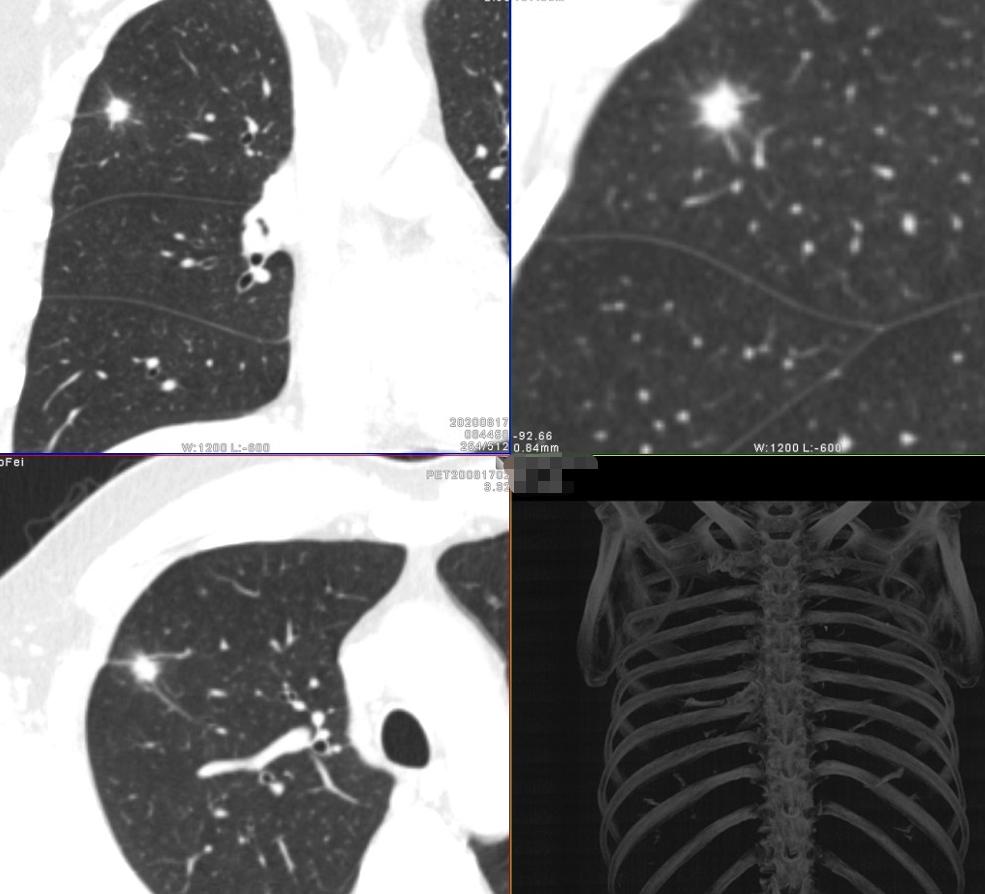

薄层高分辨三维重组图片

妥妥的恶性征象,令人心惊胆寒

影像学检查特点:右肺上叶尖段实性结节,大小1.2cm×1.1cm×1.0cm,分叶毛刺、胸膜牵拉,最主要的是有两个大的引流血管汇聚,诊断为恶性病变还需要理由吗?不需要理由。这种征象哪个医生也不敢说一定是良性的。建议活检应该是最好的选择。